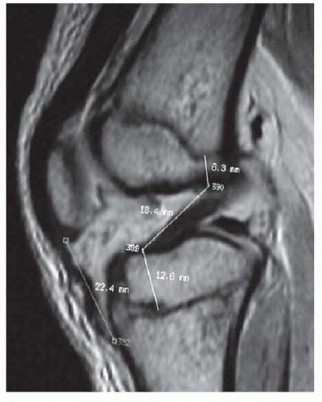

Chapter 7 Open Reduction of Supracondylar Fractures of the Humerus Christine M. Goodbody John M. Flynn DEFINI…